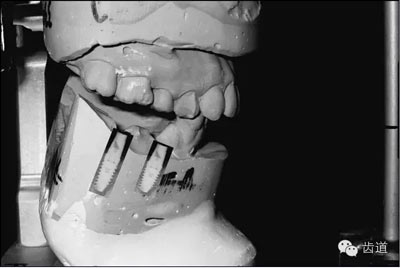

技工室

如果醫(yī)生將上HE架的工作交給了技工室,那么有關(guān)咬合記錄的工作就結(jié)束了,之后的步驟由技工室完成 。對(duì)于那些自己上HE架的醫(yī)生,我們來進(jìn)一步說明怎么進(jìn)行下面的步驟。將平板電腦放置于底座,并放置于模型前方大約6-12英寸,啟動(dòng)軟件。將上頜模型放置于HE架的上頜體上(圖10)。調(diào)出之前拍攝的患者照片。

10.jpg

圖10:模型照片

調(diào)整上頜模型的傾斜度,使之與圖像上的各個(gè)標(biāo)志點(diǎn)位置重合。確認(rèn)中線,切嵴,HE平面與面部參考點(diǎn)的位置(圖11)。

將模型調(diào)整到正確位置后,拍攝一張照片。如果需要,可以對(duì)所拍攝照片調(diào)整大小和位置,然后保存。通過調(diào)整面部照片和上頜模型照片的透明度,可以再次確認(rèn)上頜模型的位置是否正確,然后將上頜模型固定于HE架上的上頜體。打開有關(guān)咬合關(guān)系的記錄(圖9),并據(jù)此將下頜模型放置于正確的位置,然后在HE架上固定?! ?/p>

此時(shí),VF軟件中有了三張圖像,一張是顱面部的參考圖像,一張是患者的面部照片,還有一張是上頜模型的照片。通過調(diào)整任何一張圖片的透明度,進(jìn)一步確認(rèn)三者之間位置的正確性(圖12),從而保證最終上頜模型在HE架上處于正確的位置。技工室的操作部分到此也就全部完成了(圖13)。在視頻網(wǎng)站YouTube上有相關(guān)的操作視頻,可以查看(圖14)。

12.jpg

圖12:顱面部參考圖像,患者面部照片和上頜模型照片重疊的截屏

13.jpg

圖13:VF軟件指導(dǎo)下完成的模型上HE架